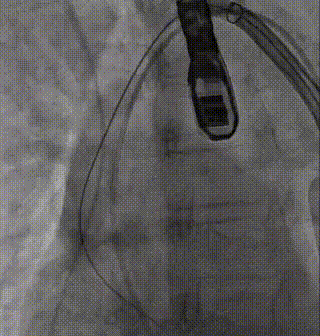

过弓

部分释放